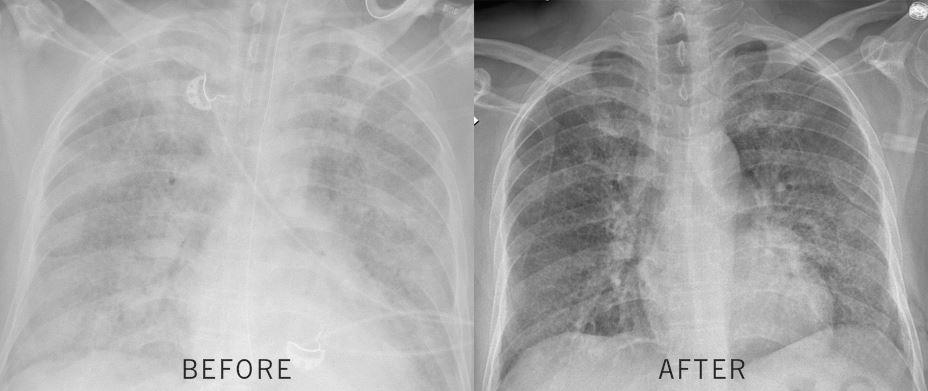

Physicians at Cleveland Clinic Abu Dhabi have performed the UAE’s first whole lung lavage procedure to remove protein deposits in a patient’s lungs, enabling him to breathe freely again.

The patient, M.M., had found that his breathing had been getting progressively worse and he was admitted to a hospital in Al Ain. After a month in intensive care, a biopsy found the cause of his worsening condition. He was suffering from pulmonary alveolar proteinosis (PAP), a rare lung condition that causes protein deposits to build up in the alveoli of the lungs, blocking the transfer of oxygen into the blood.

As the saline drained, it washed the protein deposits away, clearing the way for his lung function to return to normal. The team used 26 liters of saline during the procedure.

Following the successful procedure, M.M was transferred to the cardio-thoracic ICU. The following day, he was disconnected from the artificial lung and his breathing has returned to normal.